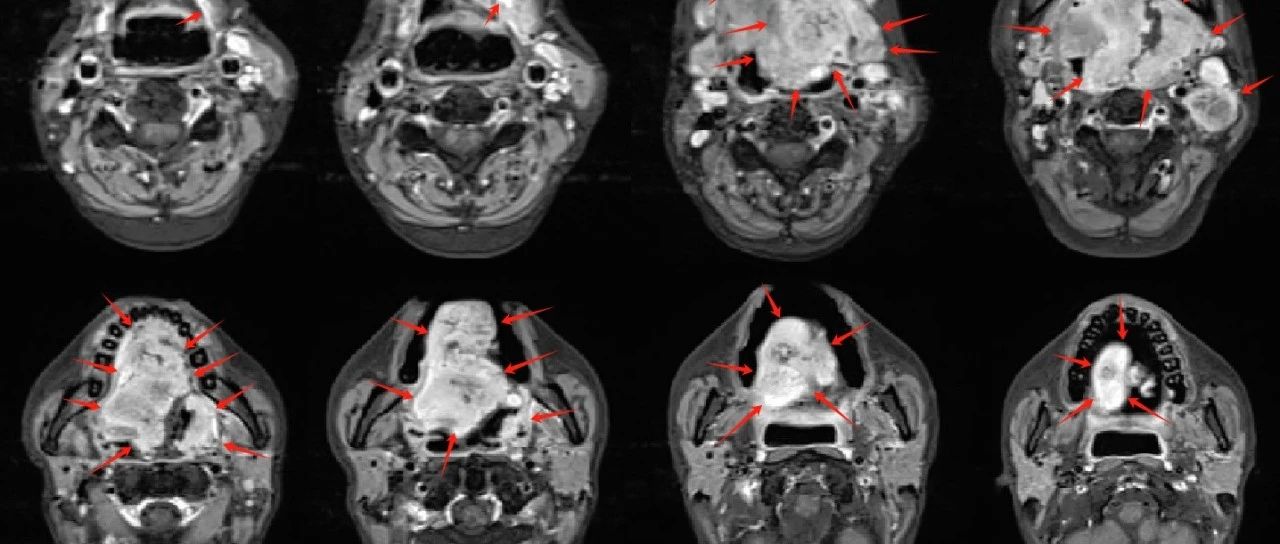

患者陳女士,42歲,半年前發(fā)現(xiàn)舌腫物,病理活檢確診舌癌。半年來經(jīng)歷多方案化療聯(lián)合免疫治療。療后短時(shí)間內(nèi),病灶復(fù)發(fā)進(jìn)展。再次行化療聯(lián)合免疫治療無效。腫瘤生長極快,侵犯整個(gè)口腔及口咽腔。磁共振檢查可見,腫瘤范圍特別巨大,全舌受侵,整個(gè)口底、上顎受侵,基本占據(jù)整個(gè)口腔;同時(shí)腫物向后侵犯口咽,并侵占口咽腔。患者極其痛苦,并多次發(fā)生腫物出血等嚴(yán)重情況。

圖注:磁共振檢查可見,腫瘤范圍特別巨大,全舌受侵,整個(gè)口底、上顎受侵,基本占據(jù)整個(gè)口腔;同時(shí)腫物向后侵犯口咽,并侵占口咽腔,病灶明顯強(qiáng)化。雙側(cè)頸部可見多發(fā)淋巴結(jié)轉(zhuǎn)移。